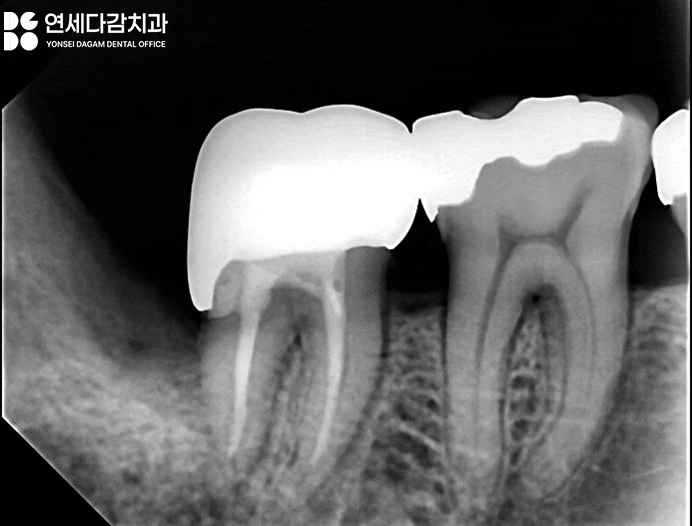

우선 원인이 된 사랑니를

빼는 것이 먼저입니다.

이 과정에서

추가 손상이 가지 않도록

조심스럽게 시행했습니다.

이미 충치로 부식이 심한 상태에서는

제2대구치의 치관이 부러지는

일이 생길 수 있기 때문입니다.

무사히 이를 뺀 뒤 근관치료를

시행했습니다.

충치로 인한 손상 범위가 넓은

경우에는 치료가 까다로울 뿐만 아니라

크라운 또한 정확하게 제작하는 것이

어렵습니다.

무엇보다 치료 후에도

불편감이 지속될 가능성이 높습니다.

이는 치아의 구조적 안정성이

이미 많이 손상되었기 때문입니다.

따라서 이런 경우에는 치료 후에도

특별한 관리가 필요합니다.